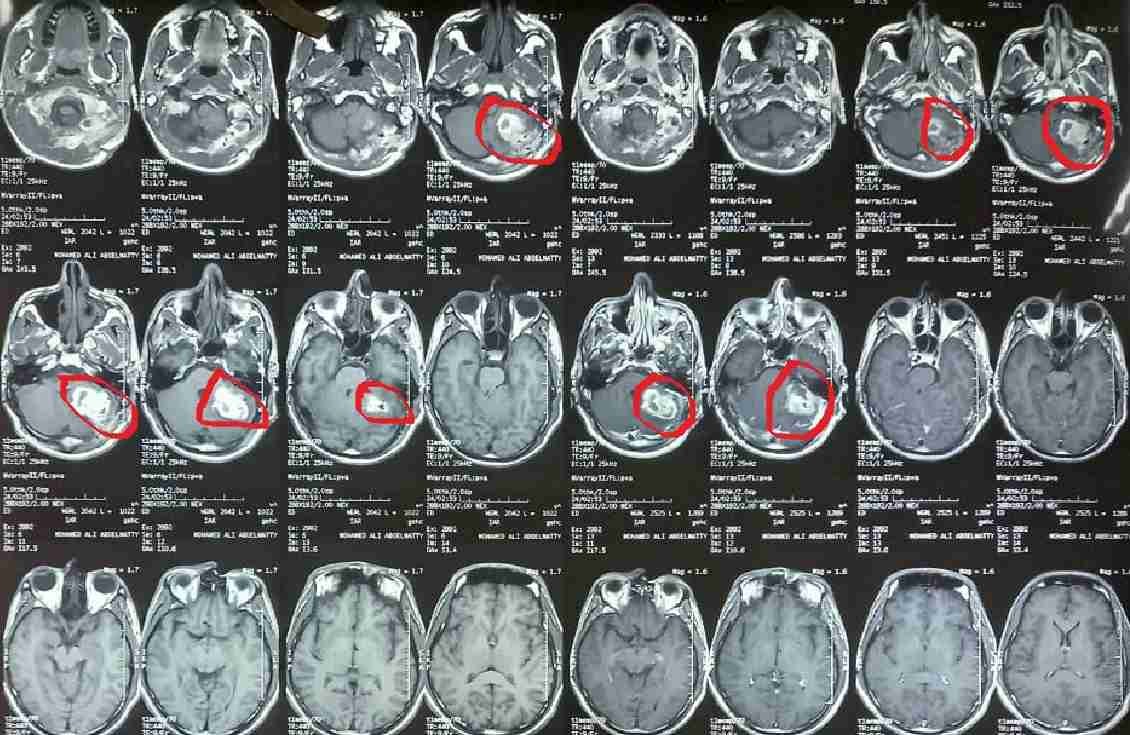

cpa  ورم بالحجرة الخلفية بالمخ مؤثر علي عصب الاتزان وعضلات الوجه

cPA is a tumor in the posterior chamber of the brain affecting the balance nerve

A successful precise surgery was performed to remove a tumor from the posterior cranial fossa, where the tumor was directly affecting the balance nerve (vestibular nerve) and the nerve responsible for facial muscle movement (seventh cranial nerve). This sensitive area controls balance, motor coordination, and facial expressions.